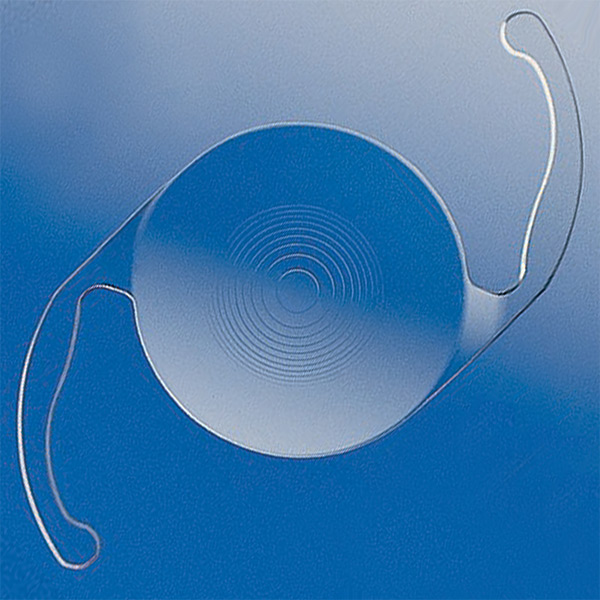

An IOL, or intraocular lens, is an artificial lens implant that can replace the eye's natural lens to improve vision. They're often used to replace clouded lenses during cataract surgery and/or to correct refractive errors like nearsightedness and astigmatism.

These lenses are very small, flexible devices typically made of silicone or acrylic, and many types can be customized to a patient's unique vision needs. Monterey County Eye Associates offers a wide range of IOLs and can provide treatment tailored to you.

Placing IOLs

IOLs are a permanent solution to cataracts and can offer long-term vision enhancement.